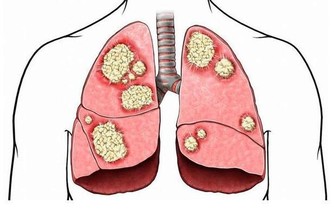

圖片翻攝自:果殼小組以及博才網 一名30多歲電腦工程師日前連續腹瀉1個月、每天拉肚子3至6次,體重狂降5公斤,檢查感染阿米巴原蟲,醫師問診發現他腹瀉前曾吃生魚片,研判是生魚片不潔引起。若生食或飲水遭含阿米巴原蟲的糞便污染,就可能感染,醫師提醒,海鮮、燒烤類食物宜熟食,要吃生魚片則應選擇環境乾淨、衛生條件較佳的餐廳。 收治病例的新光醫院消化內科主治醫師朱光恩說,該名男病患是電腦工程師,就醫時表示,原以為只是一般腸胃炎,未料竟連續腹瀉1個月、每天拉3至6次,糞便還帶有血絲及黏液,體重更從65公斤降至60公斤。 經腸道內視鏡切片檢查發現,男子腸道黏膜有阿米巴原蟲,用藥後已緩解腹瀉症狀。由於男子腹瀉前曾吃生魚片,朱光恩懷疑應是生魚片遭阿米巴原蟲污染。 衛福部疾管署首席防疫醫師羅一鈞說,阿米巴原蟲感染屬第二類法定傳染病,傳染途徑為糞口傳染,若生食或飲水遭含阿米巴原蟲的糞便污染,或手、口接觸患者肛門,就有感染風險。阿米巴原蟲進入人體後,易侵犯腸、肝、肺及腦,延誤治療恐致死,全台每年約100至200名患者,其中半數為本土患者。 羅一鈞解釋,阿米巴原蟲以吞噬紅血球維生,會破壞體內微血管,侵犯腸道即會造成腸道黏膜出血而血便,侵犯肝臟會引起肝臟發炎、化膿,而有發燒、眼白變黃等症狀,嚴重會導致腹膜炎。無論淡水魚或海水魚,只要曾置於遭阿米巴原蟲污染的水中,魚體均可能帶此原蟲,羅一鈞表示,在台感染阿米巴原蟲最常見的原因,仍是廚師雙手或製作環境未注意衛生,少數為食材受污染。羅一鈞建議若要吃生魚片,應選擇環境乾淨、衛生條件較佳的餐廳,至於吃生魚片常沾的山葵,僅能增加口感、風味,並無法殺菌、消毒或殺死阿米巴原蟲的效果。 開業胃腸肝膽科醫師張振榕說,一般腸胃炎的腹瀉約持續3至7天,阿米巴原蟲感染腸道的腹瀉可長達2至4周,且糞便帶有黏液,若腹瀉逾兩周應速就醫。此外,外出旅遊或用餐宜喝瓶裝水,別喝山泉水或用山泉水洗手後進食,海鮮、燒烤類食物宜吃熟食;如廁時若曾接觸馬桶坐墊、廁所門把,應先洗淨雙手再進食。